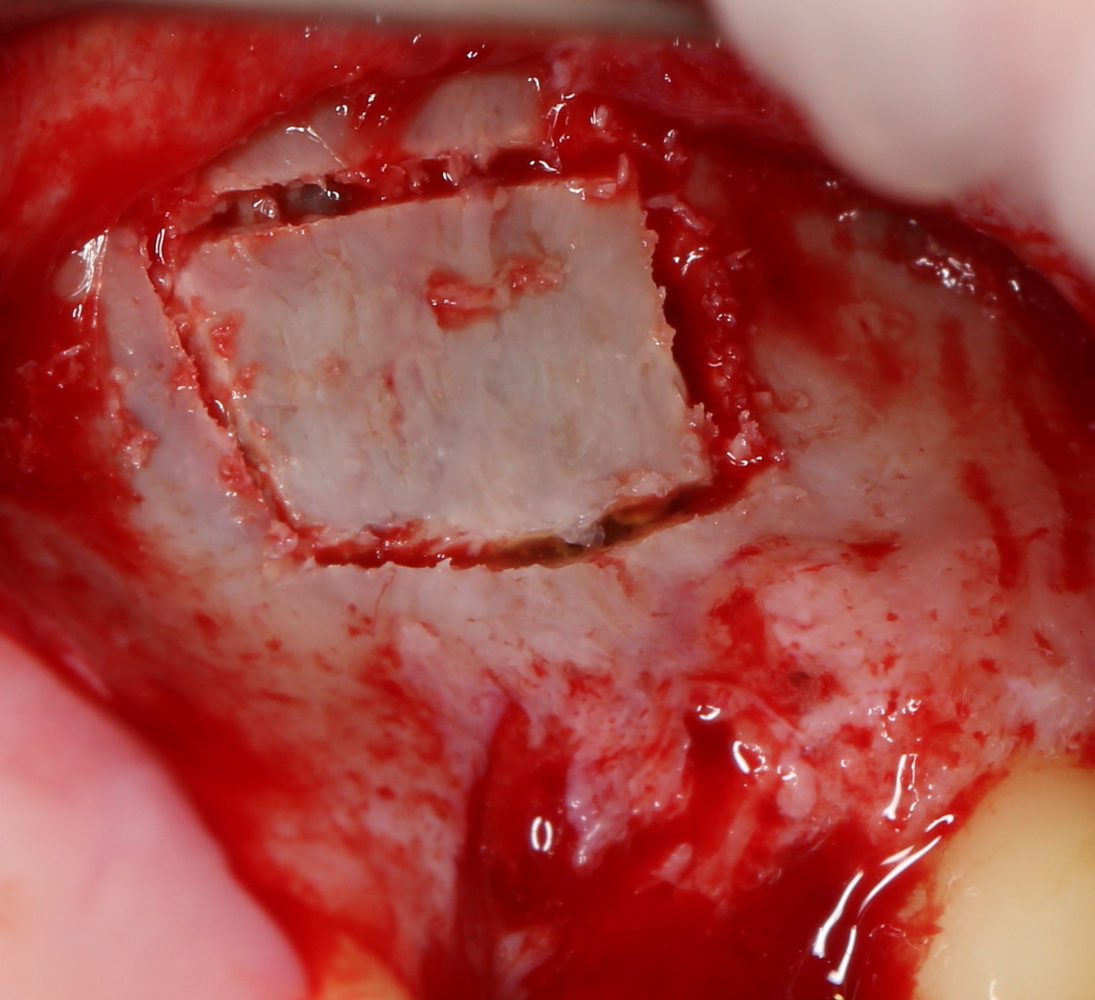

Можно долго рассуждать о преимуществах и недостатках той или иной методики, но для себя я выбрал т. н. «костнопластический доступ», который производится с помощью ультразвукового хирургического инструмента. Таким образом, мы можем создать окно в верхнечелюстную полость любой конфигурации и размера, попутно получив небольшой фрагмент костной ткани, который можно использовать как для остеопластики, так и для закрытия достаточно больших по размеру перфораций слизистой оболочки.

Рисунок 26, 27, 28. Создание доступа в верхнечелюстную полость с помощью ультразвуковой хирургической системы. Слева – процесс создания доступа, в центре – удаленный фрагмент костного окна, видна слизистая оболочка гайморовой пазухи, справа – заживление костной раны через 3 месяца.

Если получаемый при создании доступа костный фрагмент планируется использовать для остеопластической операции, то площадь окна рассчитывается, исходя из размера этого костного фрагмента. Разумеется, это возможно при адекватной толщине наружной стенки верхнечелюстной полости (рис 30, 31).

Рисунок 30, 31. При сочетании синуслифтинга с остеопластической операцией площадь окна рассчитывается, исходя из размеров необходимого для остеопластики костного фрагмента (слева формирование окна, справа – фиксация костного блока для восстановления объема альвеолярного гребня)